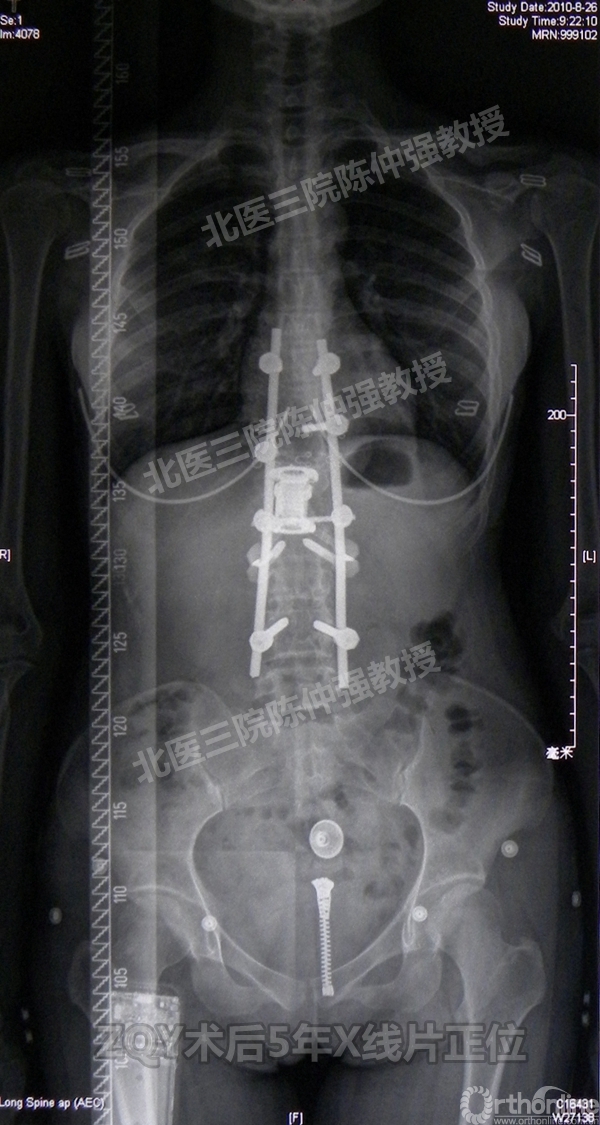

ZQY术后5

患者女性17岁,胸腰椎陈旧结核性侧后凸畸形,局部呈“麻花状”扭转,无神经功能受损表现。2005年,陈仲强教授带领团队实施后路+侧前方联合入路脊柱节段切除、双轴旋转矫形术。术后患者外观显著改善,神经功能正常。术后随访证实患者截骨矫形节段骨性融合良好,矫形效果持续良好。